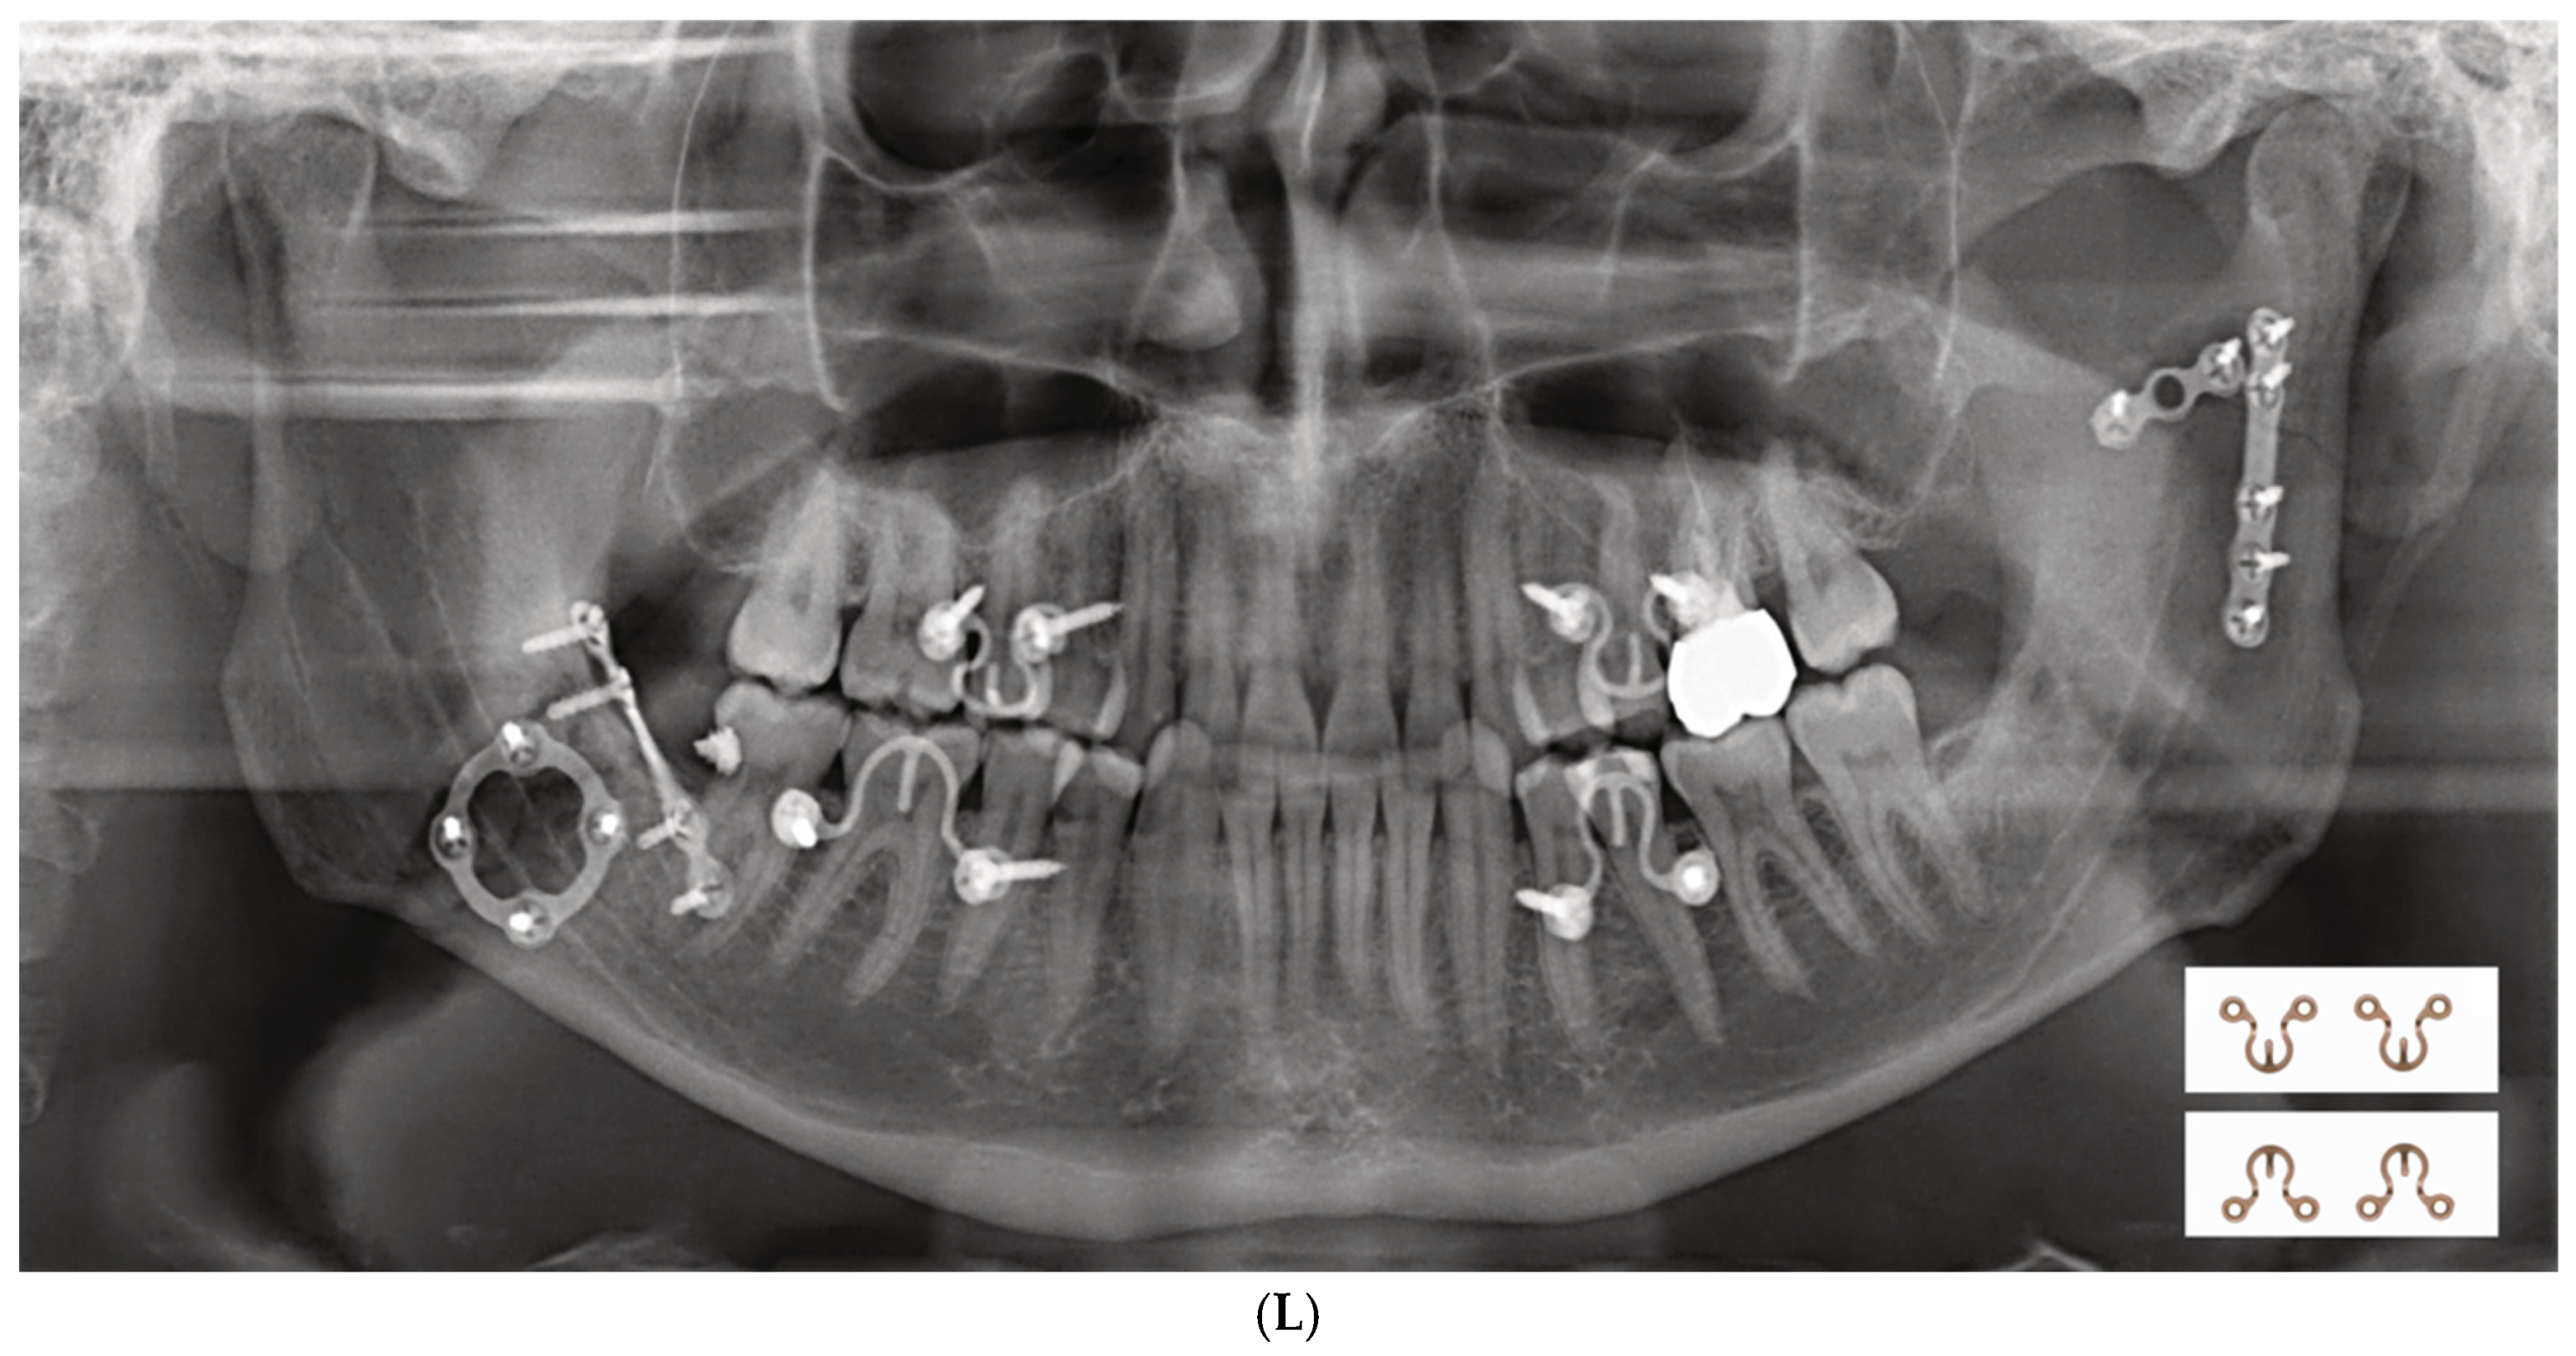

2.3. Matrix Wave System—Final Design and Technical Description

3.1. Matrix Wave Plate—Segmentation and Malleability

3.2. Matrix WaveTM Plate MMF System—Mode of Application